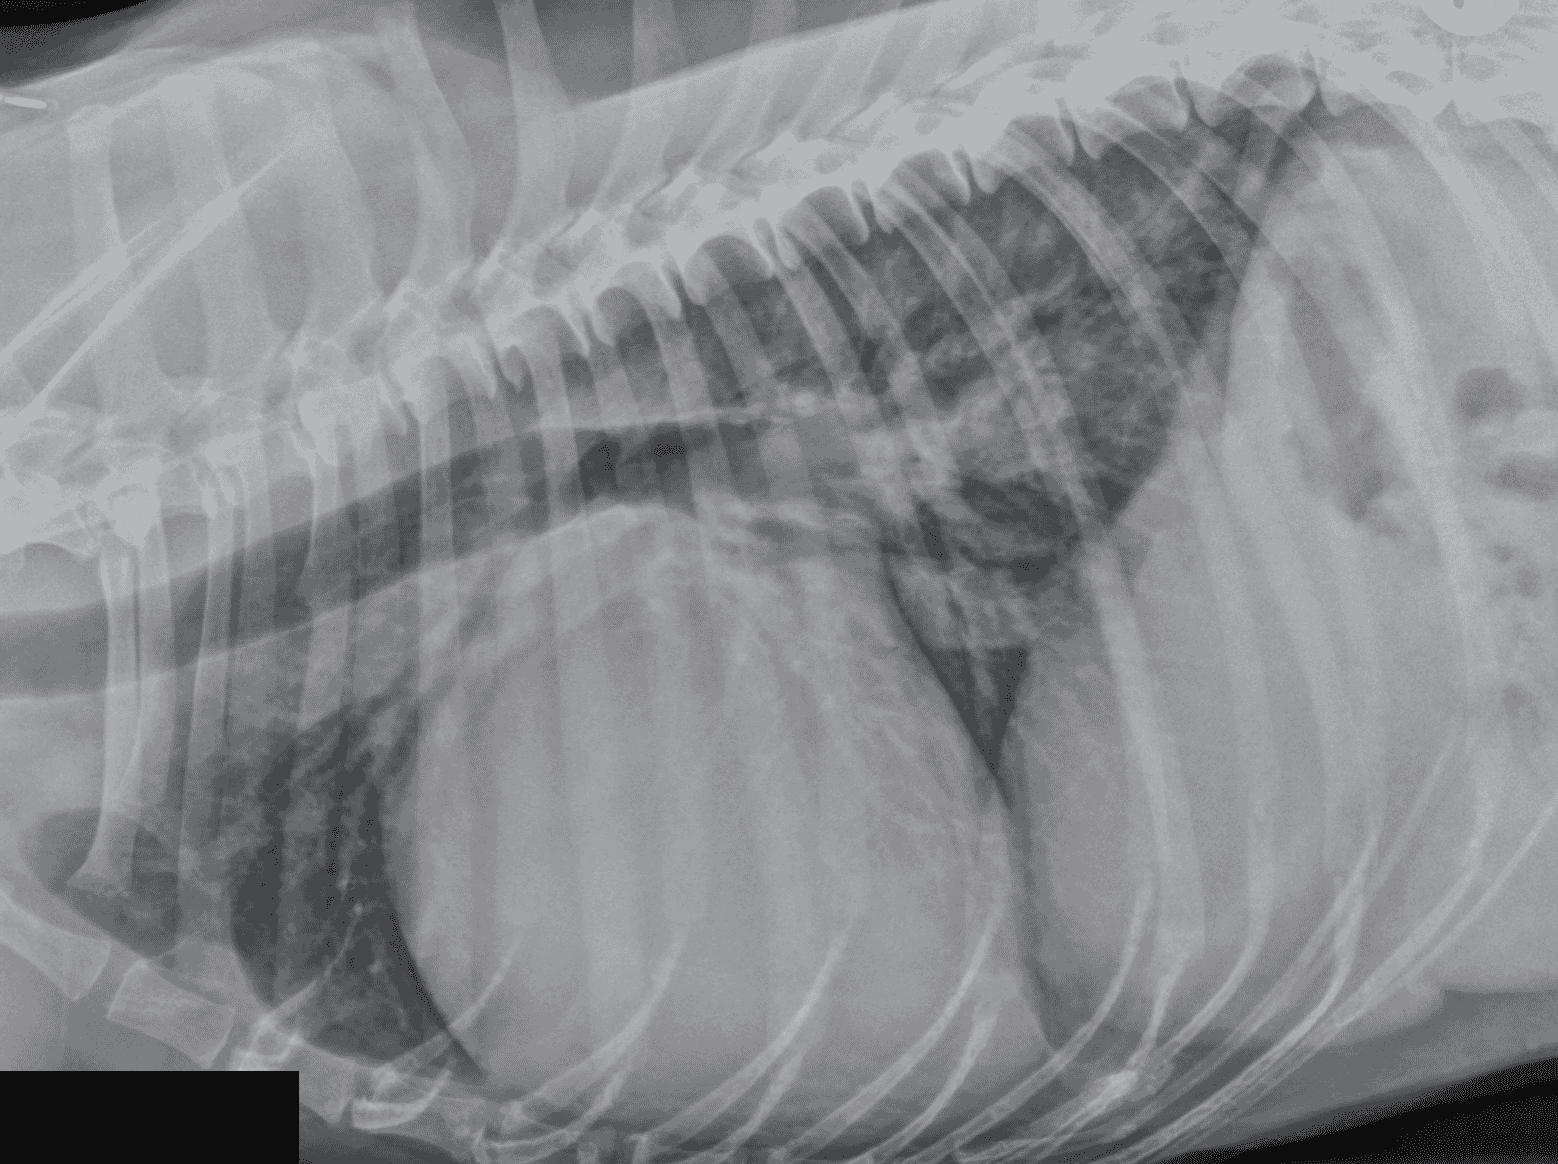

Here, we will be focusing on acute left-sided heart failure, caused by mitral valve disease (MVD) or dilated cardiomyopathy (DCM) ( Figures 1 and 2). In dogs, these make up probably 95 percent of the cases of heart failure identified in primary care practice, with the remaining being caused by arrhythmogenic right ventricular cardiomyopathy (especially in Boxers and Bulldogs), arrhythmia-induced heart failure (relatively common in working breeds) or congenital heart diseases such as patent ductus arteriosus (almost exclusively puppies of predisposed breeds).